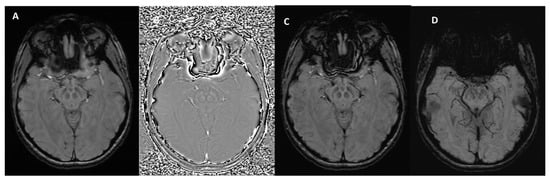

3. Technical Fundamentals of SWI